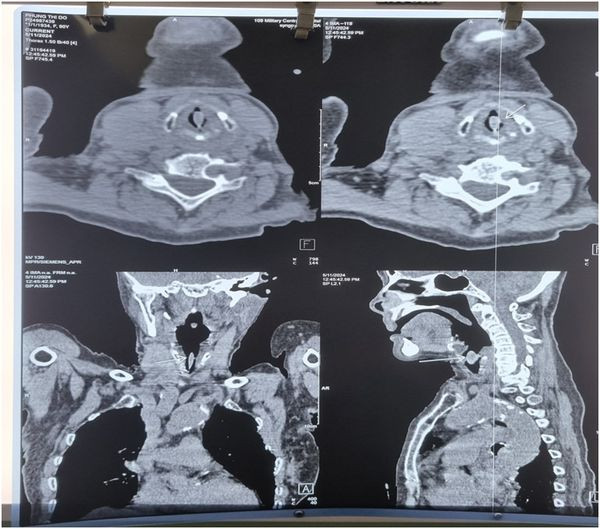

| Hạt hồng xiêm trên phim chụp - Ảnh BVCC |

Tại Khoa Cấp cứu, Bệnh viện Trung ương Quân đội 108 ghi nhận bệnh nhân trong tình trạng nguy kịch, khó thở thanh quản, thở rít, bệnh nhân tím tái, kích thích vì dị vật mắc vùng cổ. Ngay lập tức bệnh nhân được thở oxy dòng cao qua Canun mũi (HNFC- High Flow Nasal Cannula), thuốc giãn phế quản và tiến hành chụp cắt lớp vi tính xác định vị trí dị vật. Kết quả phát hiện bệnh nhân có dị vật thanh quản ngay sát dây thanh, gây tắc gần hoàn toàn đường thở.